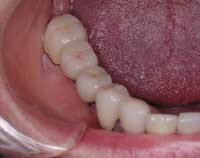

| Before | After |